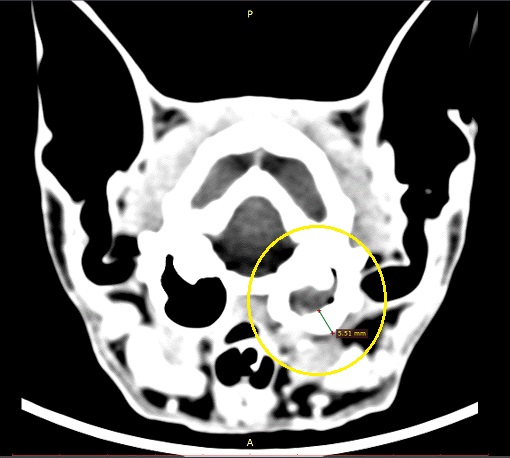

Ist das Mittelohr betroffen, spricht man von einer Otitis media. Sie entsteht im Zusammenhang mit Schnupfen oder Halsentzündungen. Bei der Otitis media kommen Störungen im Gleichgewichtssinn und eine Kopfschiefhaltung vor, manchmal hat es auch ungleiche Pupillen oder ein sogenanntes Horner Syndrom. Um eine Otits media zu erkennen, muss man das Trommelfell anschauen, manchmal röntgen, manchmal erkennt man das erst im CT was genau los ist. Aber die klinischen Erscheinungen sprechen in der Regel für sich. Bei der O.media kann man in der Regel recht gut mit verschiedenen Antibiotika behandeln, manchmal ist aber auch ein operatives Vorgehen notwendig. In solch einem Fall muss das Mittelohr eröffnet und drainiert werden. Hier ist der Fall einer 4 jährigen Maine Coon Katze “Chester”

Nachtrag: Chester haben wir zwischenzeitlich operiert. Das Ohr wurde an der Muschel verschlossen und seitlich eine neuer Seitenausgang des Gehörganges in die obere Wange verlegt. Bei dieser Operation konnte ein Polyp entfernt werden, der über das Mittelohr bis in die Eustachische Röhre sich ausdehnte und letztendlich der Grund für die Erkrankung war. Alles ist supergut verheilt und das Ohr ist endlich trocken. Durch die erhaltene Verbindung nach aussen bleiben die Hörfunktionen praktisch erhalten, die Kopfschiefhaltung ist verschwunden.